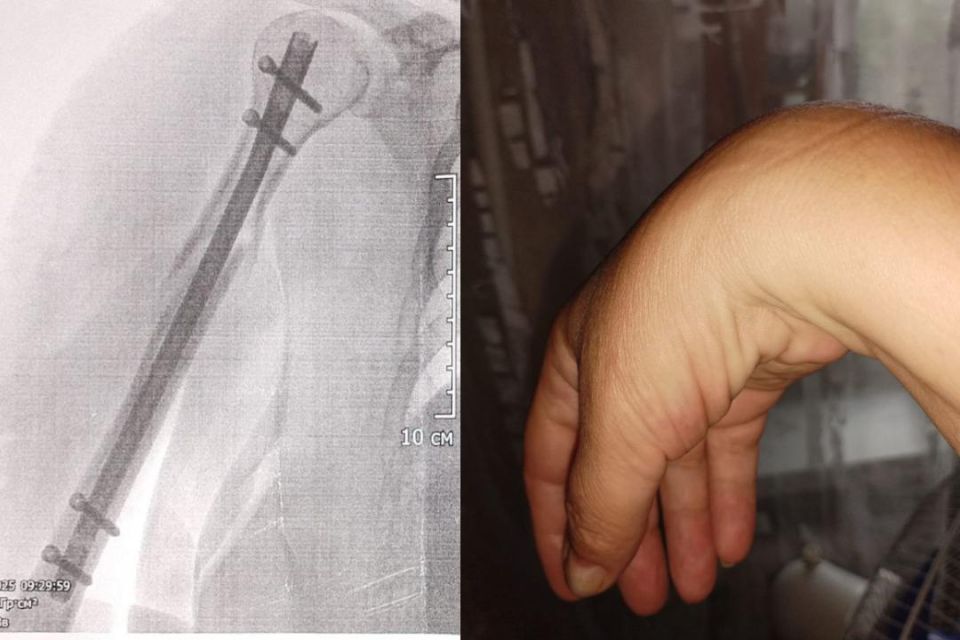

55-летняя сибирячка водной из первых пришла на работу, зашла внутрь бизнес-центра и поскользнулась на кафельном полу на не закрепленном коврике. Женщина сломала руку, ей установили титановый стержень, но правую кисть парализовало. Томские нейрохирурги...